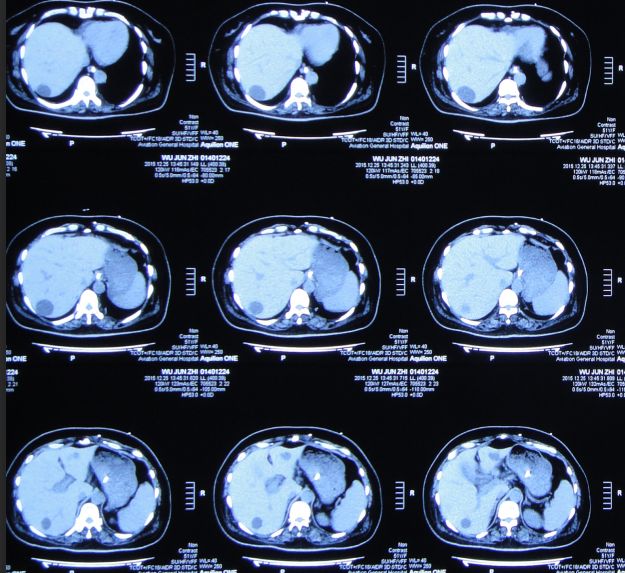

当日上午患者诉上腹部、下胸部疼痛。急查腹部CT:肝内多发囊肿;胆囊结石、胆总管结石(图32)。

图32:2015年10月27日腹部CT肝内多发囊肿;胆囊结石、胆总管结石

因两次心肌酶检查无明显变化,心内科会诊:基本可排除心肌梗死,但考虑患者有轻度冠心病可能。患者神清,精神差,呼吸急促,间断呕吐、腹痛。普外科会诊:考虑患者有胆囊结石、胆总管结石,目前症状与此有关,可采取保守治疗或手术治疗。与家属沟通后,决定暂给予抗感染、补液等保守治疗。

ERCP术后第一天即2015年10月30日,患者症状仍无改善,精神差,呼吸急促,喘憋,张口呼吸,言语不清,持续胃肠减压。白细胞:19.3*10^9/L↑,中性细胞比率:94.0%↑,血红蛋白:74g/L↓,血小板:51*10^9/L↓,白蛋白:26.3g/L↓。急查腹部CT:胆囊增大、胆囊结石。

图34:2015年10月30日腹部CT:胆囊增大、胆囊结石